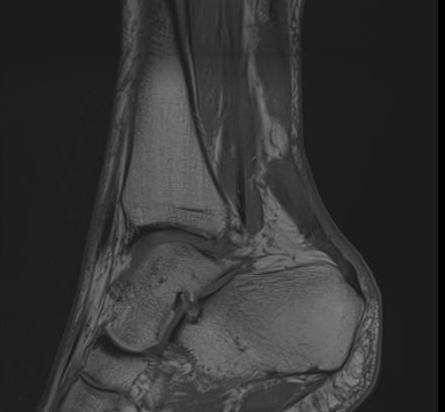

MRI

Indication

- incomplete rupture / clinical uncertainty

- chronic tears - measurement of gap for reconstruction planning

Acute

High grade partial thickness

Chronic retracted